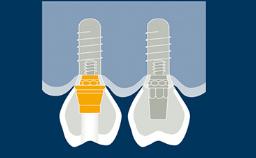

However, the complexity is higher when using implant-supported prostheses since they can have multiple components that fit together very precisely along limited paths of insertion.

In addition, these prostheses need to be delivered onto rigidly fixed implants. All these factors make this a much more exacting procedure.